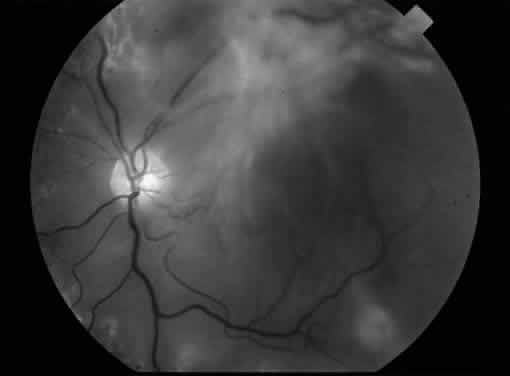

MACULAR EDEMA ASSOCIATED WITH POSTERIOR HYALOIDAL TRACTION

Fig. 6. A. Fundus photograph of an eye with vitreomacular traction syndrome. B. Fluorescein angiography showing deep, diffuse dye leakage.